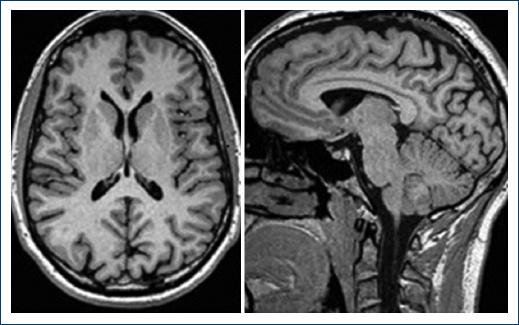

Laboratory tests where requested indicating leukocytosis with neutrophilia; slight increase in liver enzymes with partial direct hyperbilirubinemia; blood cultures, urine, and stool tests negative; antinuclear antibodies; and tumor markers negative. Additional, a serological study using automated electrochemiluminescence immunoassay indicated CMV anti-IgM: 25.17 IU/ml (positive: ≥ 22.0 IU/ml), anti-IgG: 38.9 IU/ml (positive: ≥ 1.0 IU/ml), anti-IgG avidity: 14.1% (low avidity:<15%), non-reactive serology for Epstein-Barr virus, syphilis, human immunodeficiency virus, hepatitis B or C, and the rest of respiratory viruses. A serum sample was sent to a private laboratory in Quito, using the complementary health network, to determine anti-ganglioside antibodies by semi-quantitative enzyme-linked immunosorbent assay, with positive result for GQ1b anti-IgM: 64 index value (IV) (referential interval 0-50 IV) and GQ1b anti-IgG: 141 IV (referential interval 0-50 IV). In addition, CSF was analyzed after lumbar puncture, which revealed albuminocytological dissociation: proteins: 242.3 mg/dl (normal values: 10-45 mg/dl), cell count: 10 cells/mm3 with lymphocyte predominance (pleocytosis: > 10 cells/mm3), and non-infectious or malignant pattern. Magnetic resonance imaging (MRI) of the skull reported that there is no evidence of ischemic attacks, hemorrhages, or tumors, confirming the absence of anatomic damage (Fig. 1).

Figure 1 T1 sequence brain magnetic resonance imaging, which does not show organic damage in this clinical case

MRI can show an enhancement of the nerve roots, which indicates a rupture of the blood-brain barrier due to inflammation that occurs in GBS. However, MRI is used initially to discard other quadriparesis etiologies such as transverse myelitis, amyotrophic lateral sclerosis, or intracranial disease5.